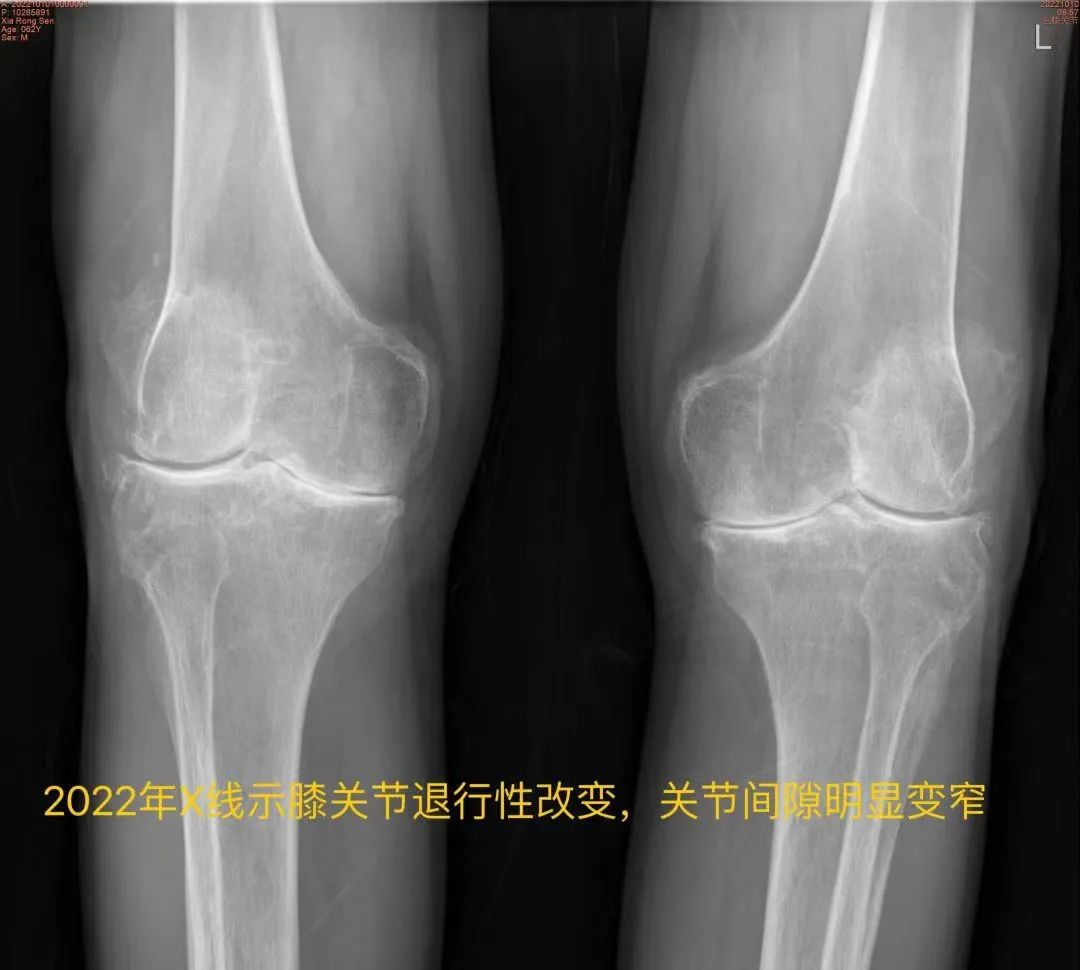

今年64岁的王大爷(化姓),双侧髋、膝关节疼痛十余年,六年前因“腰腿疼痛”于上海长征医院行腰后路减压植骨融合内固定术,同年于上海新华医院内分泌/遗传科行基因检测诊断为“黑尿病”,四年前因“左髋疼痛”于我院行“左侧人工全髋关节置换术”,一年前因“右膝疼痛”于我院行“右侧人工全膝关节置换术”。

近日,王大爷因“左膝关节步行活动后疼痛加剧”门诊拟“黑尿病性膝关节炎”再次入住我院骨科,入院后查体:全身皮肤出现黑色素沉着,以面部及耳廓皮肤黑色斑块沉着明显,左膝关节周围肿胀,有压痛,左膝关节屈曲100°,伸直约10°(正常膝关节活动度为屈曲135°,伸直0°)。